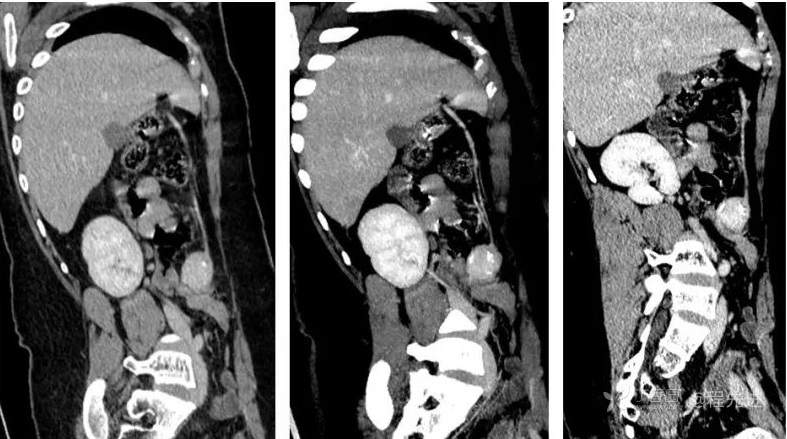

CT

图像依次为平扫(CT值46HU),动脉期(CT值138HU),静脉期(CT值137HU),延时期(CT值96HU)斜矢状位重建